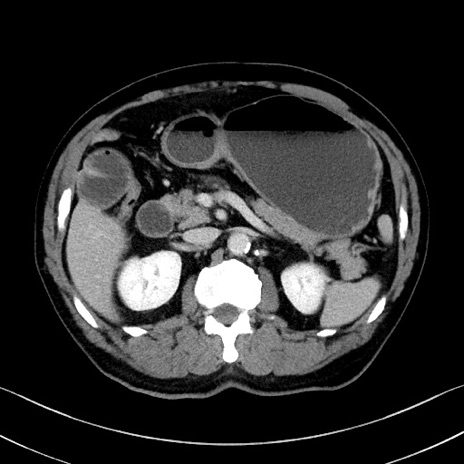

症例35(横断像)

【症例】70歳代 男性

【主訴】腹部膨満、嘔吐

【現病歴】昨日より腹部膨満感出現。本日増悪し、仙痛出現。嘔吐あり、受診。

【既往歴】糖尿病、胆摘後

【身体所見】BP 149/80mmHg、HR 74/min、BT 35.9℃、腹部:膨満、軟、圧痛なし。腸雑音減弱あり。上腹部正中切開瘢痕あり。

【データ】WBC 13500、CRP 1.72